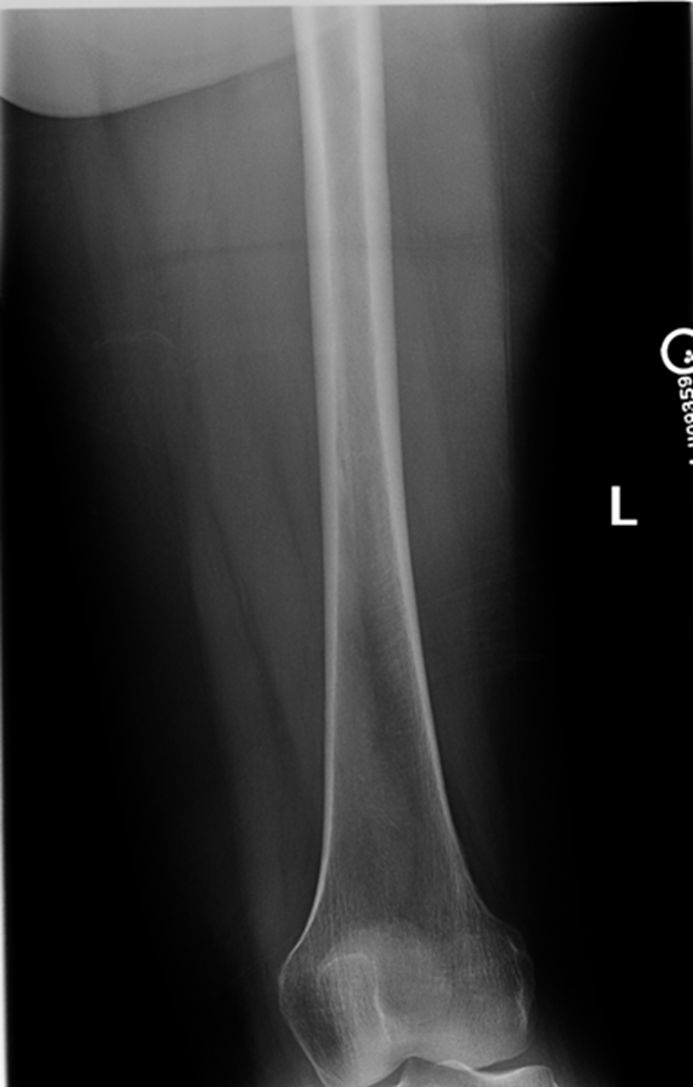

AP Femur

•Evidence of proper collimation and the presence of a side marker placed clear of the anatomy of interest

•Most of the femur and the joint nearest to the pathologic condition or site of injury (a second projection of the other joint is recommended)

•Femoral neck not foreshortened on the proximal femur

•Lesser trochanter not seen beyond the medial border of the femur or only a very small portion seen on the proximal femur

•No knee rotation on the distal femur

•Gonad shielding when indicated, but without the shield not covering proximal femur

•Any orthopedic appliance in its entirety

•Bony trabecular detail and surrounding soft tissues

Lesser trochanter is on, leg is not rotated in, under-rotated, hanging out too laterally

Leg was not internally rotated

No repeat, lesser trochanter can hardly see

Missing anatomy

slight medial rotation